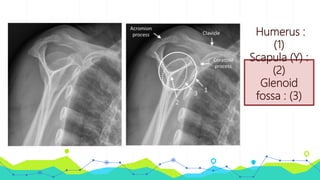

Radiogra

phic

anatomy

Humerus :

(1)

Scapula (Y) :

(2)

Glenoid

fossa : (3)

Humerus : (1) Scapula (Y): (2) Glenoid fossa : (3)